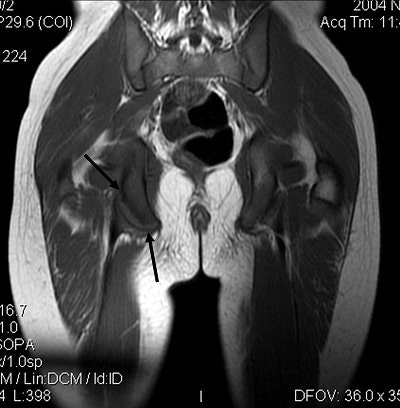

![]() |

Figure 4. Coronal T1-weighted MR image optimally shows the fracture line between the ischial tuberosity fracture fragment and the remainder of the ischium (black arrows). All images courtesy of Adam D. Sharp and Dr. Douglas Beall.